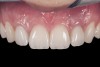

(2.) After orthodontic alignment of teeth and bleaching. Note alveolar deficiency in right lateral incisor site and diminutive left lateral incisor.

Figure 2

A 14-year-old patient presented to the office with his mother (Figure 1). His chief complaint involved the large spaces between the teeth created by his missing right maxillary lateral incisor and his small left maxillary lateral incisor. He desired to replace the missing tooth with an implant and create a beautiful smile. Upon examination, he was found to have a class I canine and molar relationship, but because he had a tooth size/arch size discrepancy and space distal to the right central incisor, the remaining incisors had drifted to the right. The left maxillary lateral incisor was peg-shaped and in a cross bite position. Studies have shown a clear association between congenitally missing teeth and reduced tooth size.59-62 Because he was only 14-years-old at the time and could not have implants placed until the cessation of growth (somewhere in the vicinity of 22 years old), he was sent to the orthodontist for alignment of the teeth.16,17 After 2 years of orthodontics, the appliances were removed, and his tooth coloration was improved using carbamide peroxide bleaching (Figure 2). Because some form of provisional needed to be placed until he was finished growing, a double-wing metal resin-bonded bridge was chosen. As discussed earlier, this is the ideal transitional prosthesis for patients that have congenitally missing maxillary lateral incisors. The benefits of this type of prosthesis include its ability to be removed and rebonded during the surgical phase of treatment and its ability to retain the roots in their proper position after orthodontic treatment.16 The final plan for the patient was to increase the width of the central and the maxillary left lateral incisor, utilizing porcelain laminate veneers to achieve the appropriate width/length ratio of 80%. A wax-up was created to idealize tooth size, a putty matrix was made from the wax-up to facilitate bonding of the incisors, and a non-precious, double-wing metal resin-bonded bridge was fabricated for lateral incisor replacement. Once the teeth were bonded to ideal size, the “Maryland Bridge” was fabricated from a polyvinyl arch impression with the newly bonded teeth (Figure 3). The metal frame was cast from a non-precious alloy to allow for fabrication of a very thin frame and to create a better surface for bonding. After sandblasting the internal aspect of the frame with CoJet™ silica (3M ESPE), accomplishing salinization, and executing cementation with a dual-cure resin cement, a fairly good adhesion to the frame was anticipated.29 The enamel surface was etched with phosphoric acid for 30 seconds, the primer (Single Bond Plus, 3M ESPE) was applied to both the internal surface of the sandblasted framework and the etched enamel, and the bridge was cemented with RelyX™ ARC (3M Espe) dual-cured resin cement (Figure 4 and Figure 5).